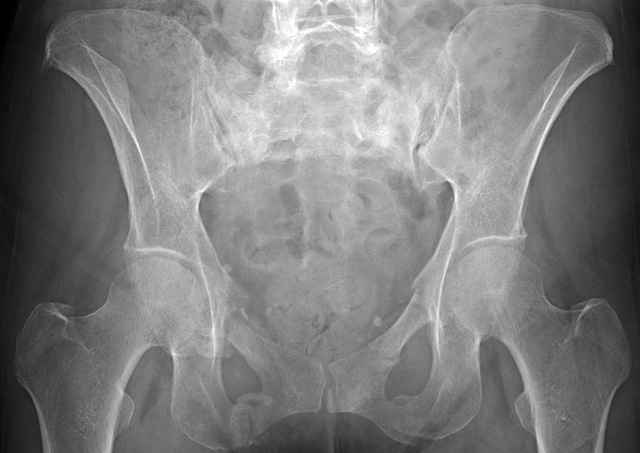

54 yo Female Fell c/o Pain

Initial Films

?Instability on Exam - Limited by Pain

NonOp Initial Mgmt